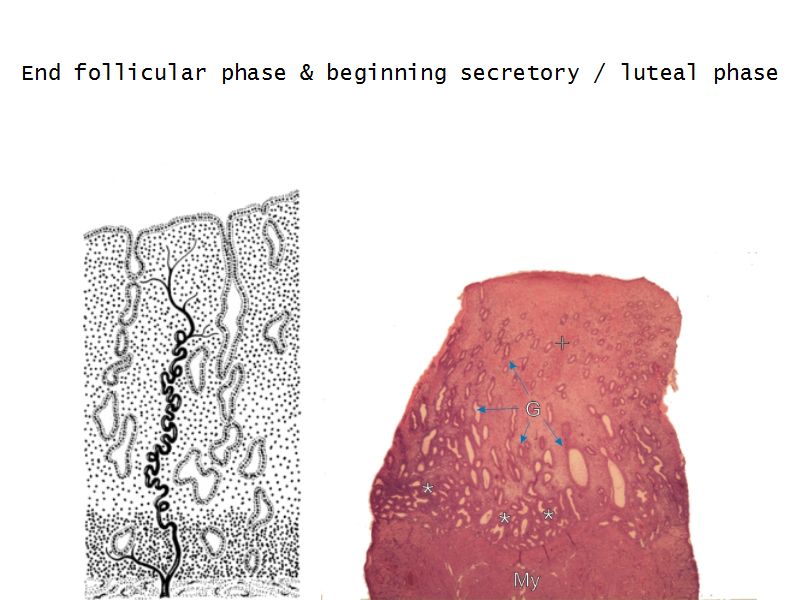

Menstrual cycle

- Follicular phase

Follicular phase

- Epithelium reform

- Proliferation of

- Glands

- Connective tissue

- Blood vessels

- Glands become coiled

- Helical arteries 2/3 into endometrium

Luteal phase